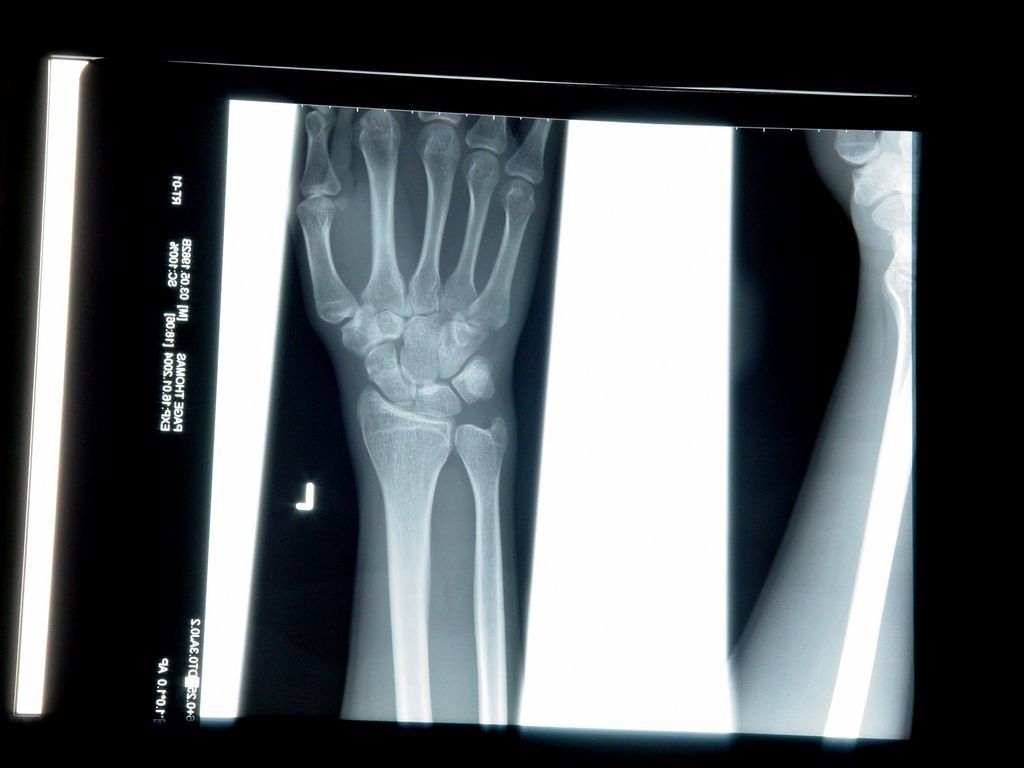

ABD’de Food and Drug Administration (FDA) tarafından onaylanan cihazın özdevinimli öğrenme algoritmaları, iki boyutlu röntgen filmlerini inceleyerek bilek kırıklarındaki temel işaretleri belirliyor ve bu işaretlerin üzerinde titizlikle çalışıyor. FDA Imagen tarafından geliştirilen cihazın doktorların yerini almayacağının altını çizerken, asıl amacın teşhisi kolaylaştırmak olduğunu vurguluyor.